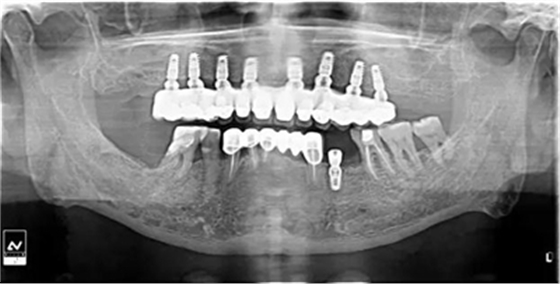

牙列缺失患者由于支持、固位、穩(wěn)定不足導(dǎo)致義齒效果差,如果在牙槽嵴內(nèi)植入種植體,種植體可以根據(jù)種植體數(shù)量不同提供義齒不同程度的固位、穩(wěn)定、支持,獲得不同的修復(fù)效果。當(dāng)單頜牙列缺失患者使用1-2顆植體,植體和覆蓋義齒之間可以靠一些附著體如磁性附著體、桿卡式附著體、球帽式附著體等裝置連接,主要提供固位和穩(wěn)定作用,少量的支持作用,當(dāng)單頜牙列缺失使用4顆植體時,很大部分支持力可以由植體承擔(dān),當(dāng)使用4顆以上植體時可完全由種植體提供義齒的支持、固位和穩(wěn)定,甚至制作為不可摘戴的全口固定種植義齒。